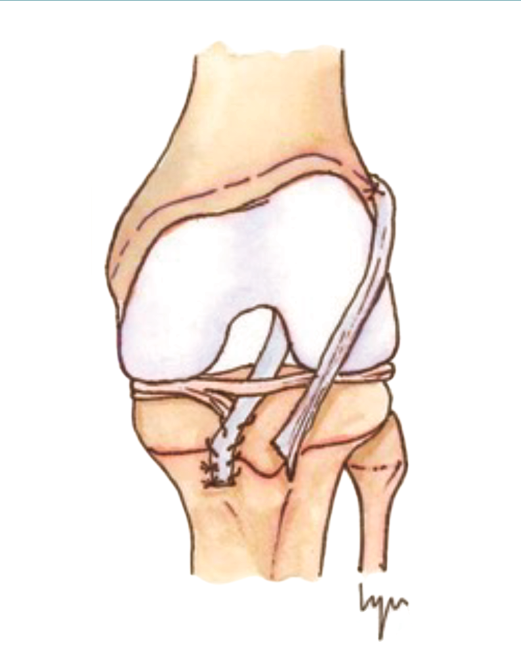

Las técnicas de “ahorro fisario” o physeal sparing

Figura 3. Técnica de la banda iliotibial.

Estas técnicas evitan la agresión de la placa fisaria. Una de las primeras fue descrita por MacIntosh y Darby(11), y modificada posteriormente por Micheli(68), conocida como la técnica de la “cintilla iliotibial” (illiotibial band –ITB–). Utiliza parte de la cintilla iliotibial como autoinjerto, dejando su porción distal unida al tubérculo de Gerdy. Es una técnica no anatómica, extra-intraarticular, en la que el injerto se pasa alrededor y por detrás del cóndilo femoral externo, en la posición over-the-top, a través de la escotadura y, posteriormente, por debajo del ligamento intermeniscal para, finalmente, fijarlo en el periostio de la tibia distal a la fisis.

Desde el punto de vista biomecánico, esta técnica proporciona una mejor estabilidad anteroposterior y rotacional en comparación con las técnicas de reconstrucción “todo epifisaria” y “transtibial over-the-top”, aunque se ha observado que puede aumentar la constricción del compartimento externo con la rotación en ciertos grados de flexión(70)(Figura 3).